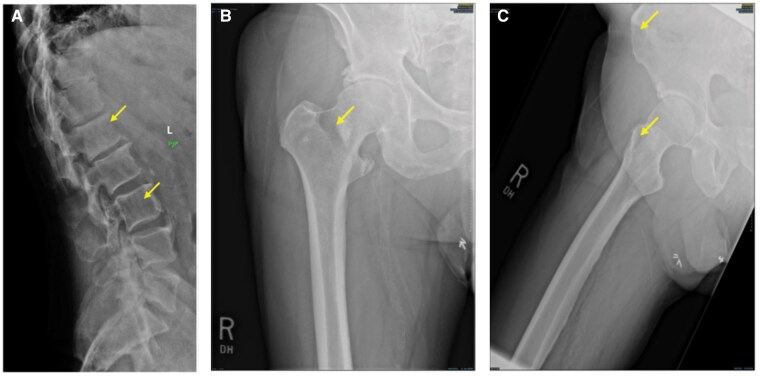

多发性骨髓瘤是一种浆细胞疾病,除了骨髓瘤疾病的其他体征外,还可导致标志性的骨破坏性变化。影像通常有助于确定诊断和患者分期。有几种不同的成像方式可以提供对疾病程度的不同程度的了解。我们报告了一个独特的多发性骨髓瘤病例,其中患者疾病的进行性突出了不同成像方法的优势和局限性。全身MRI是一种非对比成像技术,可以直接对骨髓空间进行成像,从而可以在皮质和小梁破坏性变化发生之前进行疾病检测。通过这样做,全身MRI提供了远远超过传统平片甚至CT的洞察力。利用多种不同成像方式(平片、CT、PET-CT和全身磁共振成像)的发现,我们将讨论成像如何帮助临床医生更好地评估患者的疾病负担,并补充传统疾病监测的基础(血清学、活检组织病理学、直接临床检查和观察)。

Multiple Myeloma represents a plasma cell disorder that can result in hallmark bony destructive change in addition to other signs of myelomatous disease. Imaging often helps in establishing the diagnosis and staging the patient. There are several different imaging modalities that can provide different levels of insight into the disease extent. We report a unique case of multiple myeloma where the progressive nature of the patient's disease highlights the strengths and limitations of the different imaging approaches. Whole-body MRI represents a noncontrast imaging technique that directly images the bone marrow space, allowing for disease detection that can precede the onset of cortical and trabecular destructive changes. In so doing, whole-body MRI provides a level of insight that far exceeds traditional plain films and even CT. Using the findings from many different imaging modalities (plain films, CT, PET-CT, and whole-body magnetic resonance imaging), we will discuss how imaging can help clinicians to better assess the patient's disease burden and complement the foundations of traditional disease monitoring (serology, histopathology from biopsy, direct clinical exam, and observation).